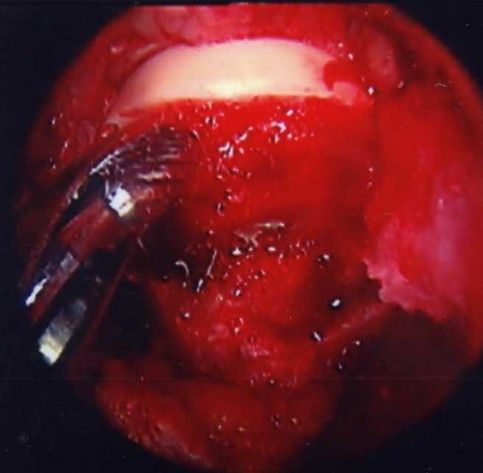

Visualisation of the central compartment of the joint for chondral and labral lesions is performed arthroscopically. After having applied distraction of the leg a 3.5 mm arthroscope (70° optics) is inserted from the anterior incision. Fluid management as in normal arthroscopy with continuous flow allows proper visualisation. The anterosuperior and lateral parts of the acetabular labrum with the adjacent articular cartilage and the femoral head are inspected. These are the areas where most of the relevant labrum and cartilage lesions are located. Depending on the amount as well as type of damage, reconstructive procedures are performed with and without traction. Ossified or ruptured parts of the labrum are resected or refixation of a partially detached labrum is performed with resorbable suture anchors (fig. 4a and 4b). Refixation of debonded cartilage flaps (fig. 5 a–d) curettage and microfracturing of damaged cartilage fragments and even autologous chondrocyte transplantation is possible (Bretschneider et al. 2020).

Contouring of the femoral head and neck by osteochondroplasty is performed with a partially covered acromionizer (fig. 6a and 6b).